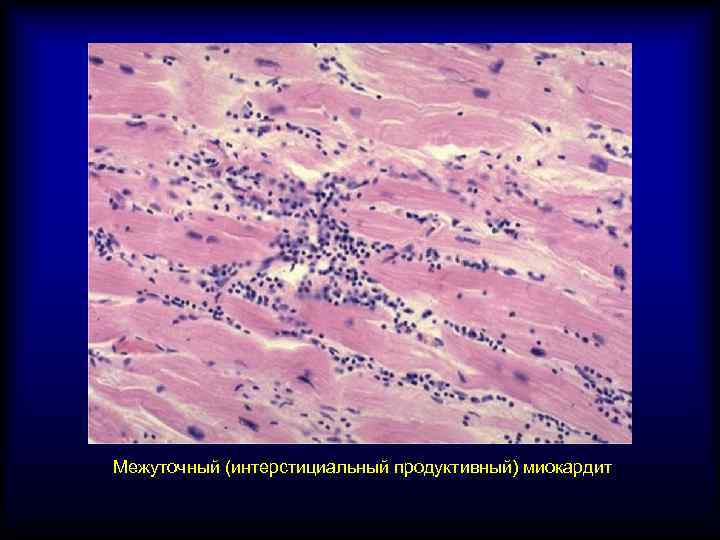

Межуточный миокардит: гистологические исследования